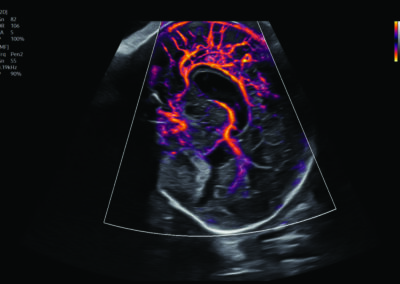

Comprehensive, advanced and expert MFM care for high-risk pregnancies

- Fetal anomalies